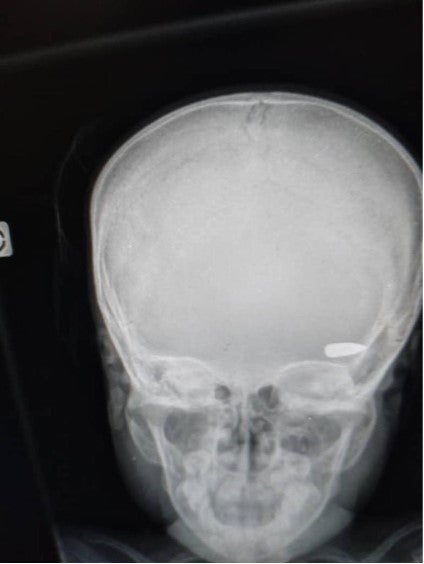

Una radiografía muestra una bala alojada en la cabeza de un niño que fue impactado durante un enfrentamiento entre grupos criminales en el barrio Brooklyn de la comuna de Cité Soleil a principios de abril de 2023.

© 2023 Privado